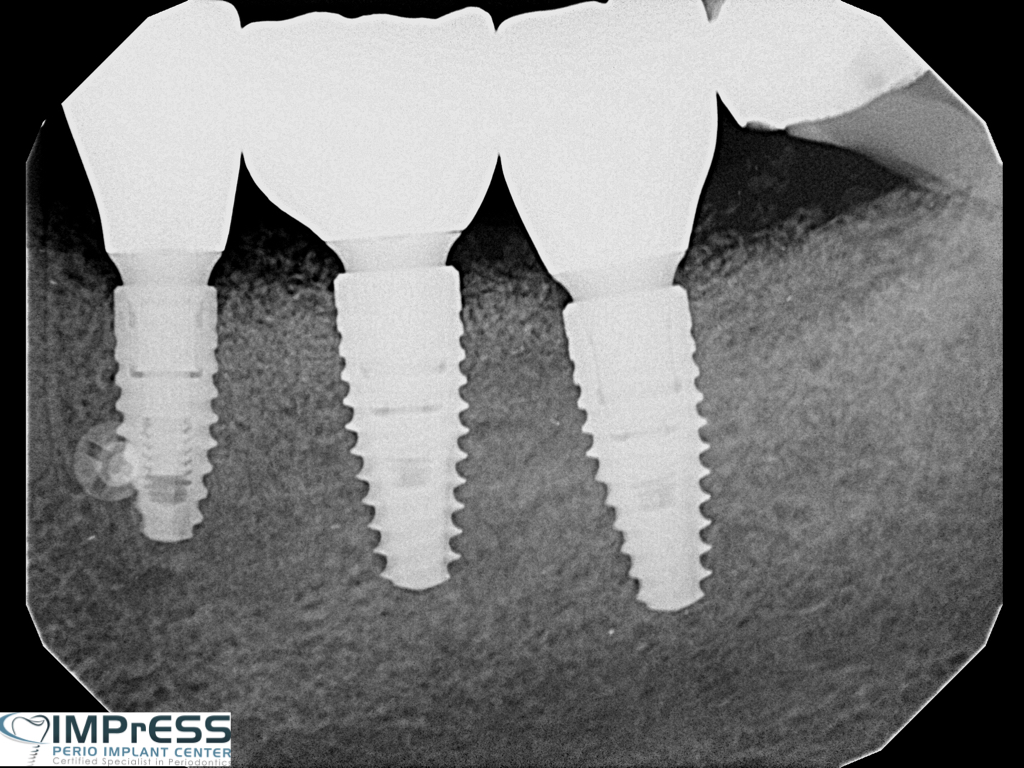

CBCT Guided Implant Surgery – Restoratively Driven Implants

Multiple Dental Implants IMPrESS Perio Implant Center Burnaby Implant Specialist Vancouver Implant Center Dr. Mehdi Noroozi Implant Specialist in BC